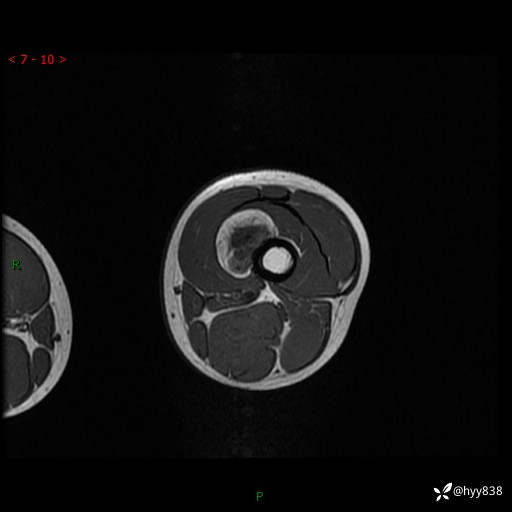

现病史:患儿3天前无意中被发现其左大腿有一包块,约鸡蛋大小,包块表面皮肤无红肿、触痛,无发热、破溃等,患儿家属当时未做特殊处理,经观察发现包块未见消退,今携患儿来我院就诊,门诊医师以“左大腿包块”收入院。 病程中,患儿神清,精神可,饮食睡眠正常,大小便通畅,体力体重无明显改变。

左大腿MRI平扫+增强